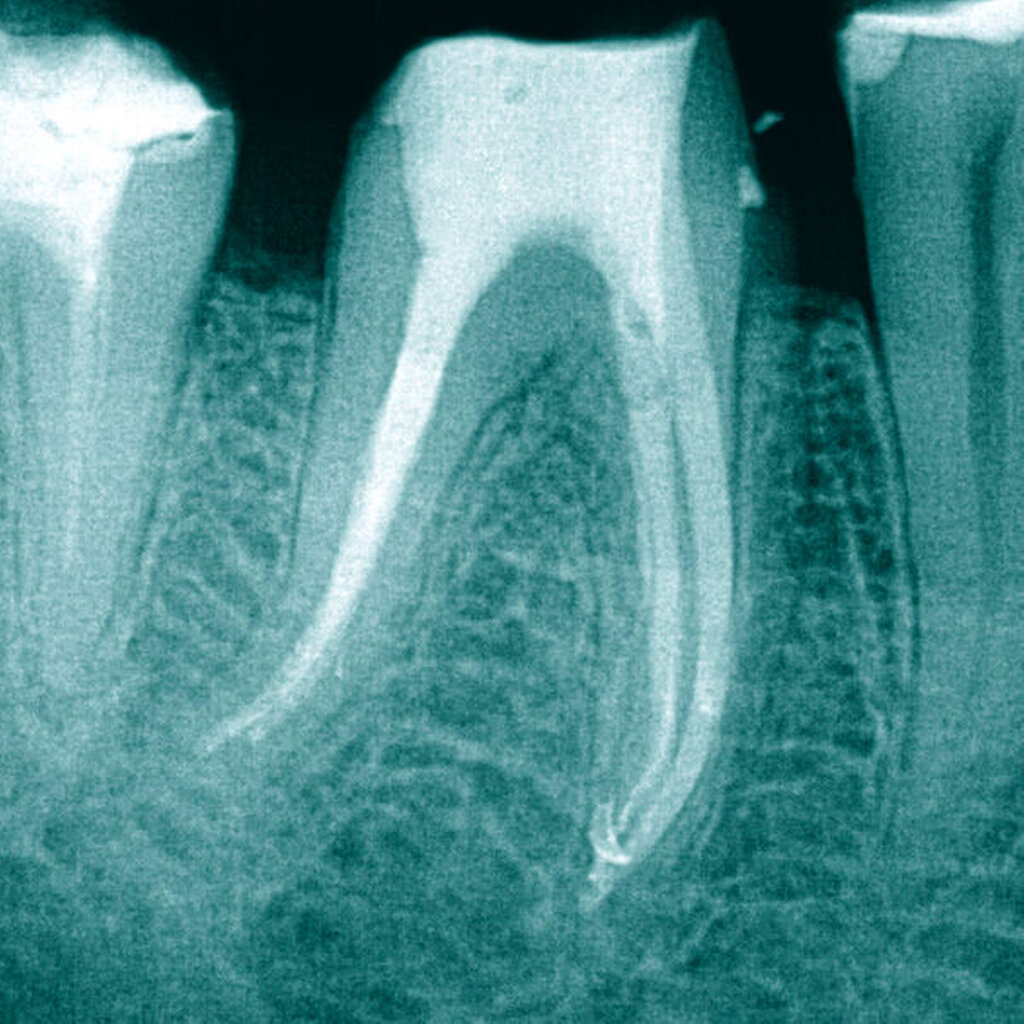

Eine 37-jährige Patientin mit einem frakturierten Nickel-Titan-Instrument in der mesiolingualen Wurzel von Zahn 36 wurde zur Weiterbehandlung überwiesen (Abbildung 6).

Mit einer Reciproc R25 (VDW) wurde zuerst die koronale Wurzelfüllung (Abbildung 7) entfernt, anschließend wurden die Kanaleingänge erweitert. Wie bei Fall 1 wurde zunächst das Fragment circa 3 mm koronal mittels Ultraschalltechnik (VDW Ultra/Endo Chuck) freigelegt und mit der oben beschriebenen Technik entfernt (Abbildung 8).

Auch in diesem Fall konnte in allen drei Wurzelkanälen Durchgängigkeit erreicht werden. Die chemomechanische Aufbereitung und Obturation (warm-vertikal modifiziert nach Schilder) der Wurzelkanäle erfolgte in zwei weiteren Sitzungen (Abbildung 9). Nach acht Monaten erfolgte der erste Recall, wobei eine deutliche Heilungstendenz erkennbar war (Abbildung 10).